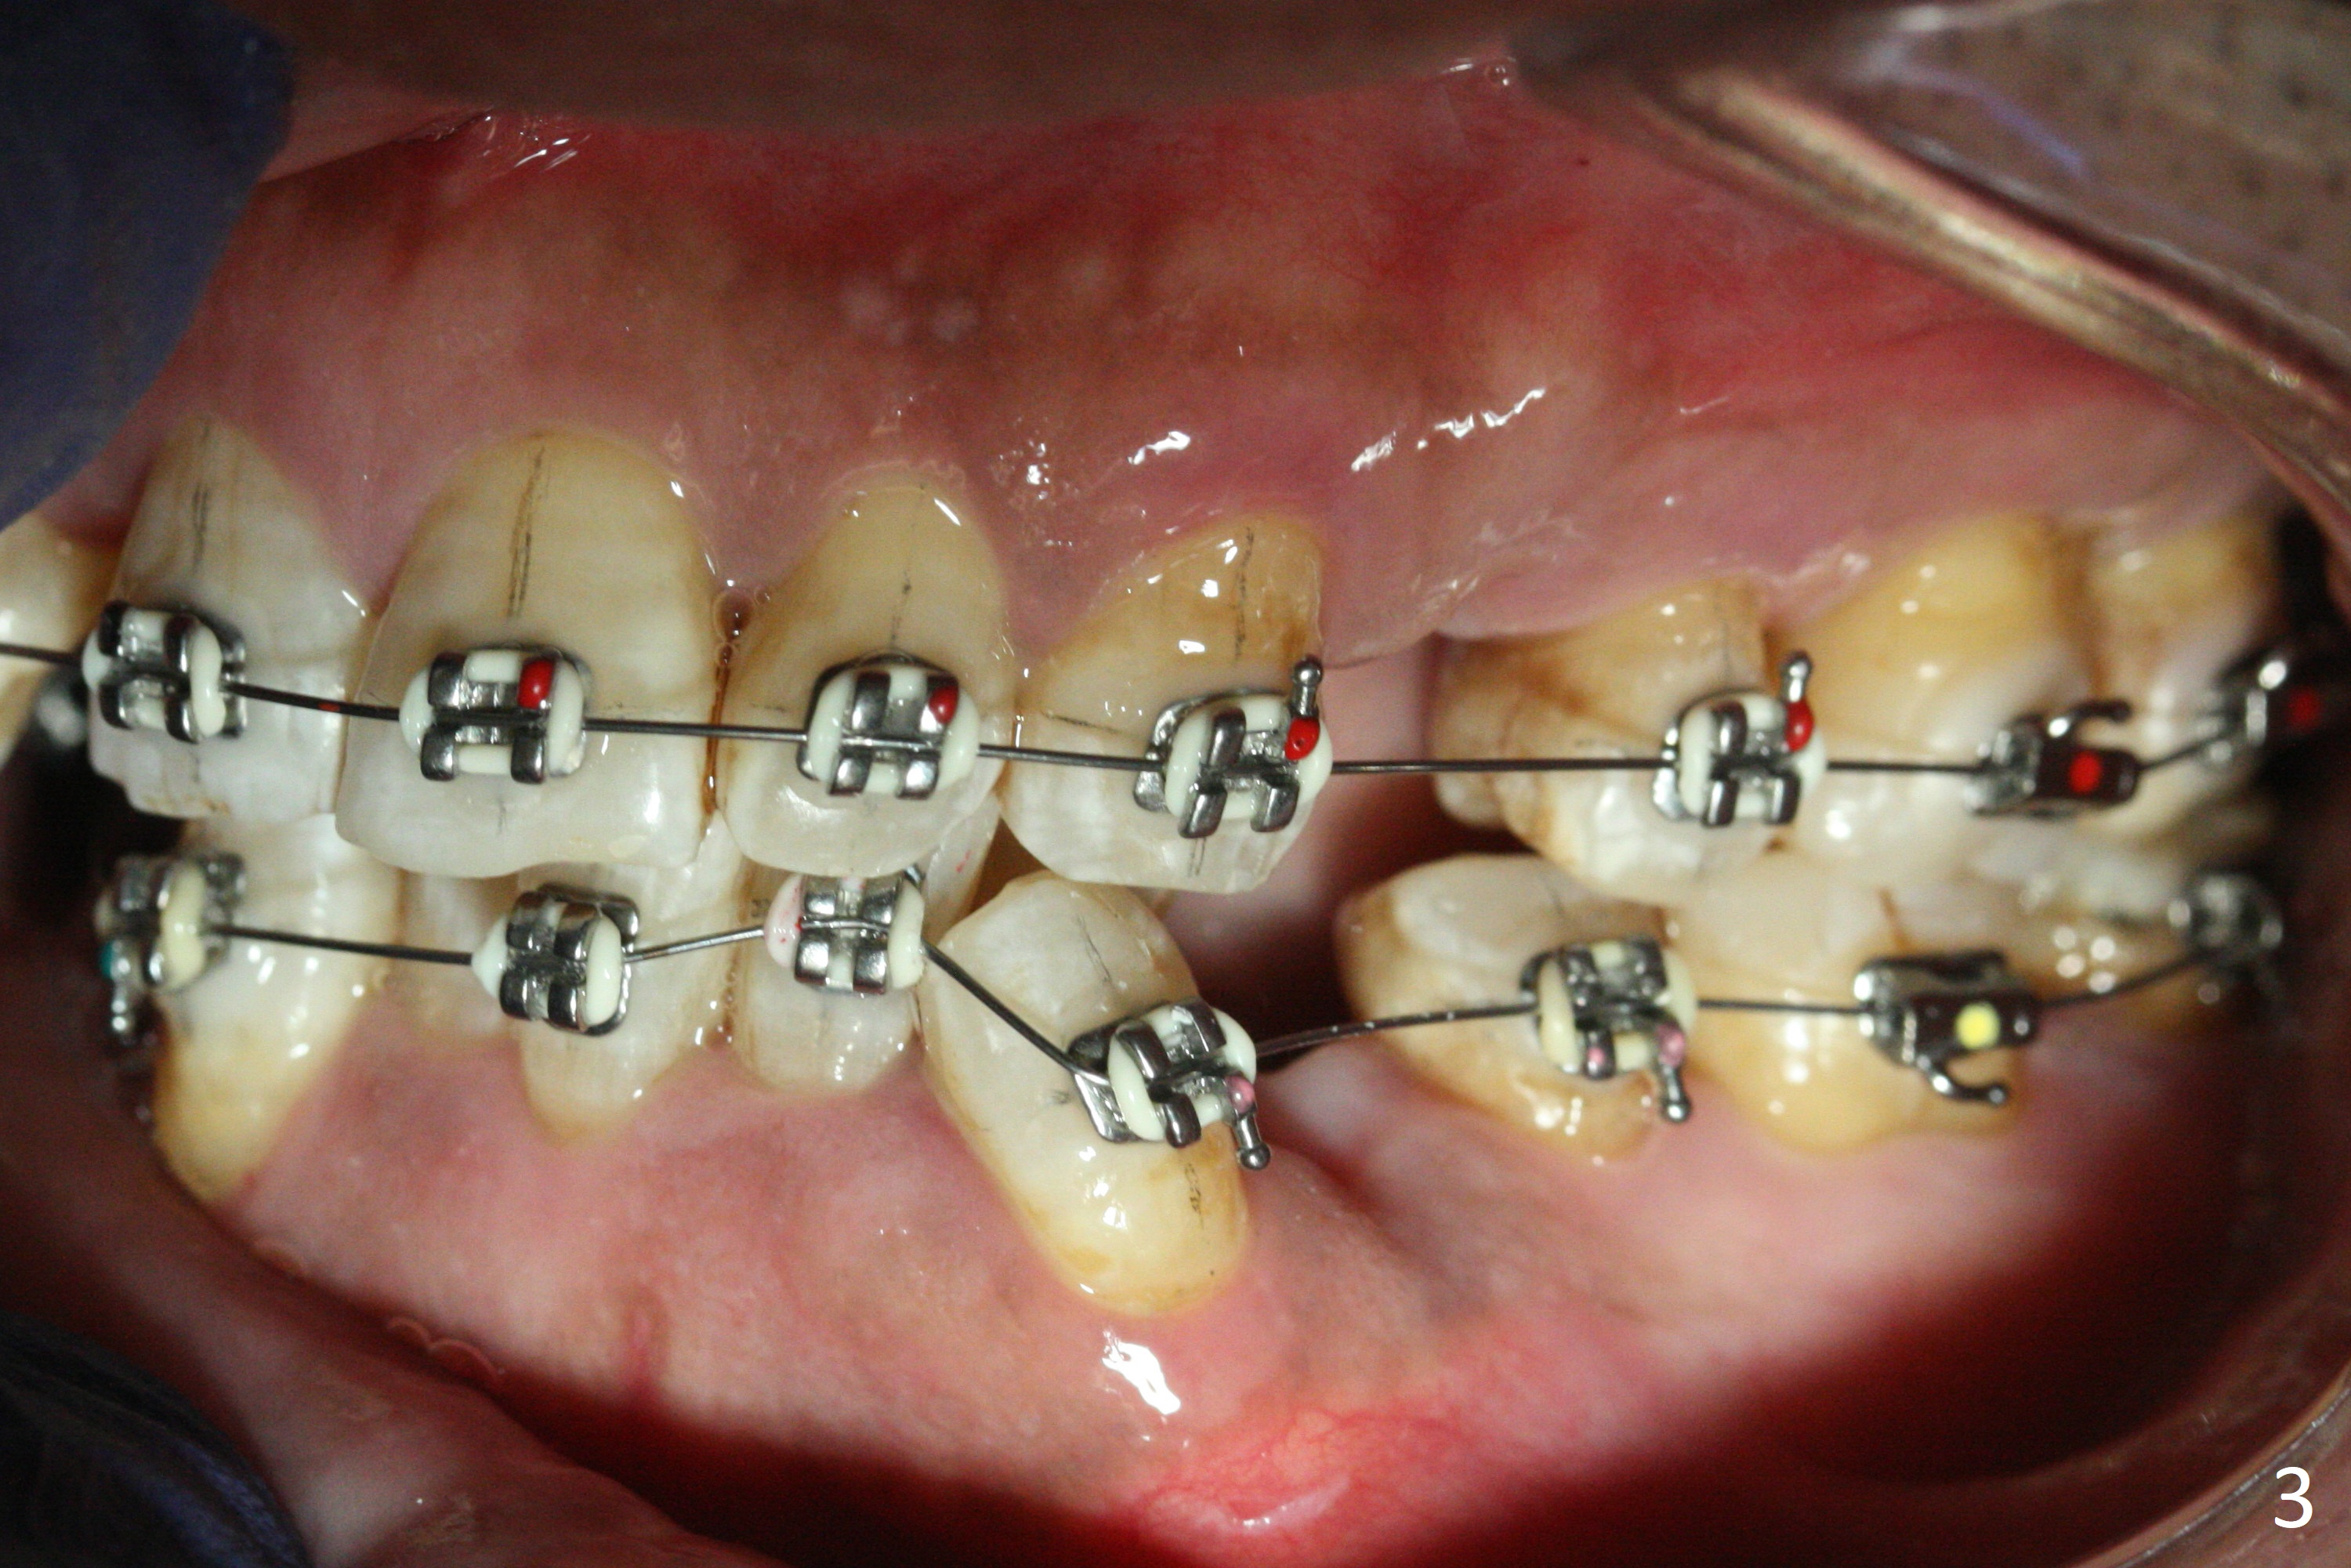

A few days post Water Pik use, the gingival erythema subsides substantially, a sign of cooperation (Fig.1 ^, as compared to earlier). Because of tight contact and loss of rubber separators due to use of water flosser, molar brackets have to be used except LR (Fig.1-3). There is enough space for UR2 bracket 5.5 months post banding. While keeping open and closed springs at UR, place sling shot for UR2. There are 2 purposes. One is to keep expanding the space for UR2, since the sling-shot tends to close the space. The second rationale is to continue mesializing UR1 to correct the upper midline deviation.

While LL3 has been distalized, there is not enough space to buccalize LL2. Extra space will be gained by continuing distalizing LR3. Consider using 7s instead of 6s as anchorage for closed springs for all of the 4 quadrants.